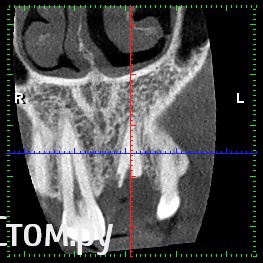

rezo47 Опубликовано 16 октября, 2014 Поделиться Опубликовано 16 октября, 2014 (изменено) Добрый день, возможно ли применение такой методики при такой клинике? Изменено 16 октября, 2014 пользователем rezo47 Ссылка на комментарий

Дмитрий Никитюк Опубликовано 16 октября, 2014 Автор Поделиться Опубликовано 16 октября, 2014 Добрый день, возможно ли применение такой методики при такой клинике?Одного КТ для обсуждения подобных вопросов мало, но ситуация более благоприятна, чем в случае из стартового сообщения. Давайте фото и описание случая, можно будет обсудить детально. По позиционированию имплантата: позиционируйте его более нёбно, чем это сделано в программе. 3 Ссылка на комментарий